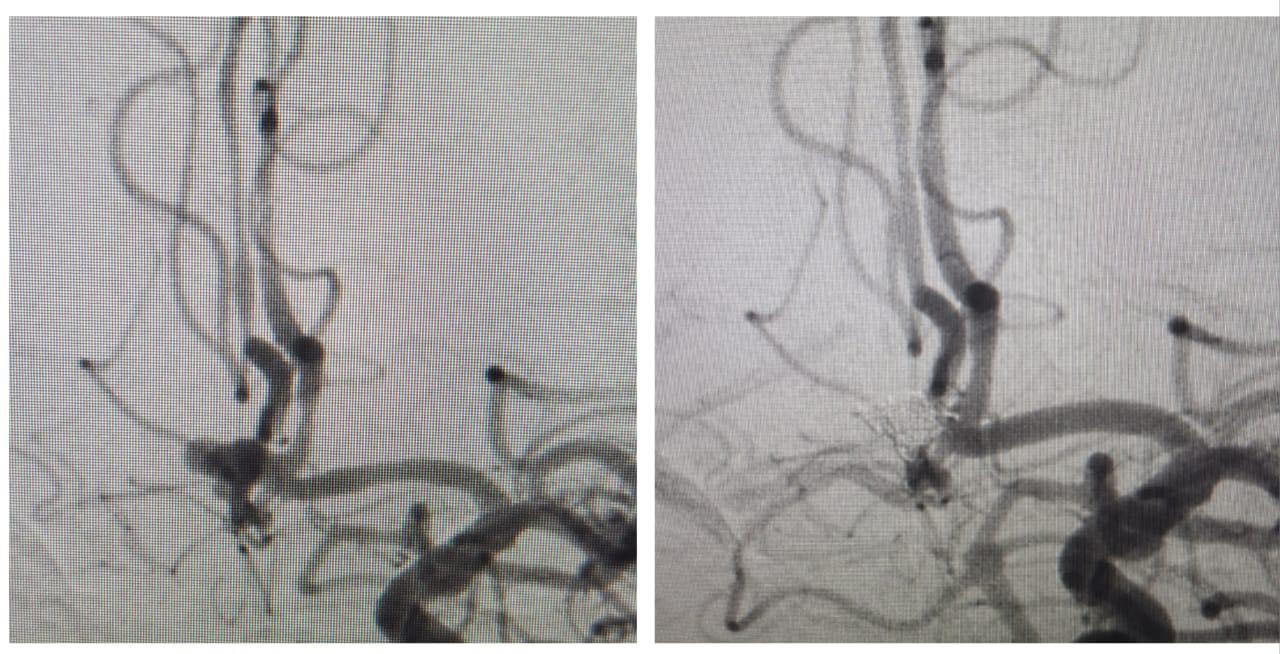

Қалалық жедел шұғыл көмек көрсету ауруханасы нейрохирургия бөлімшесінде алдыңғы қосылғыш артерияның қап тәрізді аневризмасының жарылуы салдарынан болған ауқымды субарахноидалды қан құйылу диагнозымен түскен 1962 жылы туған науқасқа жоғары дәлдіктегі рентгенэндоваскулярлық ота сәтті жасалды.

Мамандар аневризмаға рентгенэндоваскулярлық эмболизациялау әдісін қолданып, қайталама қан кетудің алдын алып, науқастың өмірін сақтап қалды.

Ота 60 минутқа созылып, еш асқынусыз өтті.